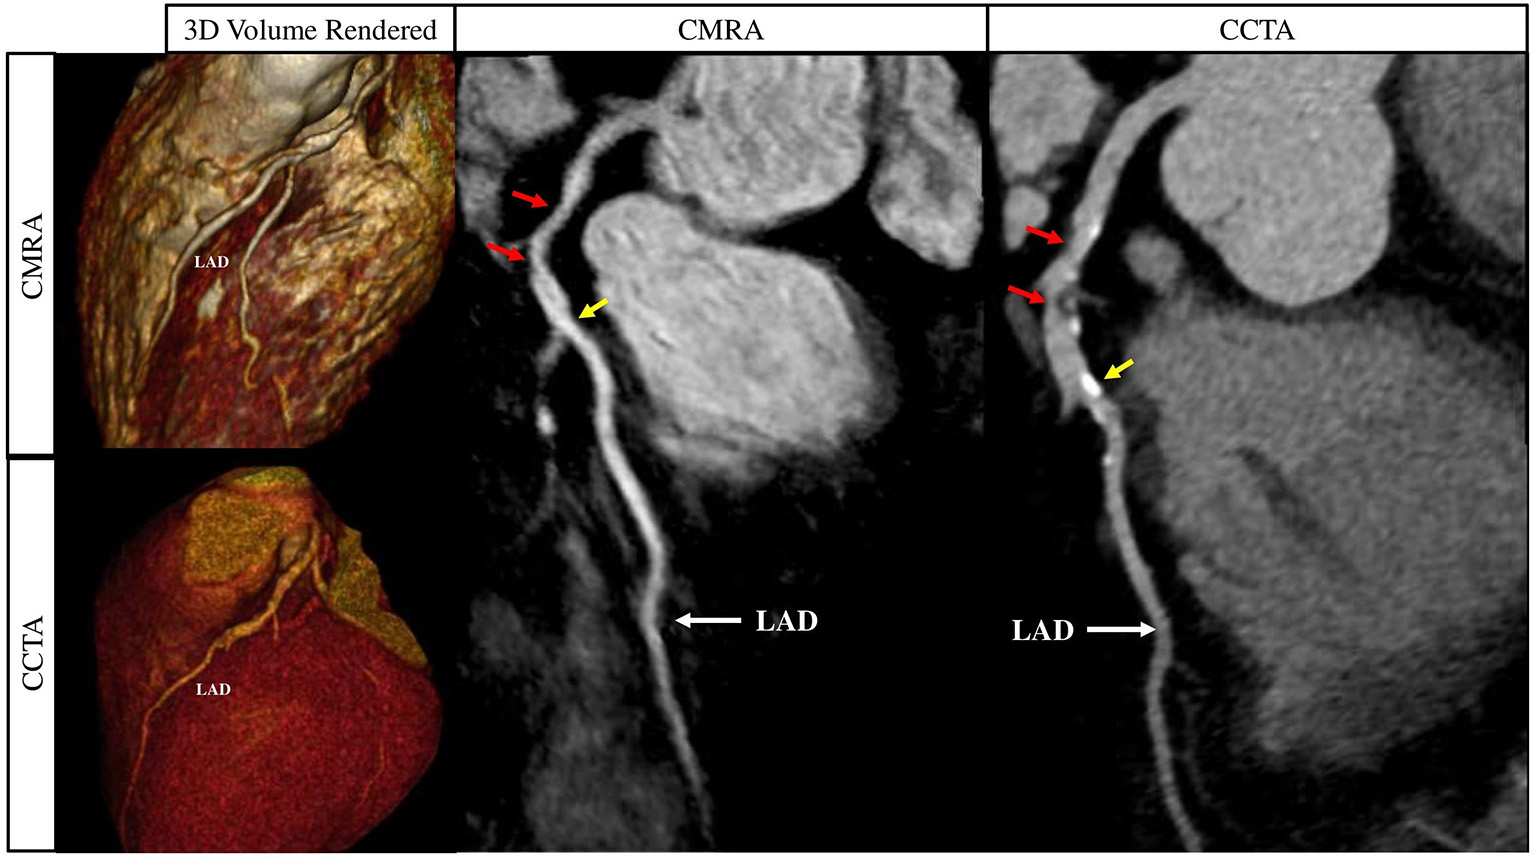

Figure 10

Curved multiplanar reformat and 3D volume rendered non-contrast CMRA and contrast enhanced CCTA in a 60 year old male with >50% partially calcified stenosis in the proximal to mid LAD on either side of the first diagonal artery (red arrows). The yellow arrows represent a focal calcified <50% stenosis just distal to the second diagonal artery. CMRA, Coronary Magnetic Resonance Angiography; CCTA, Coronary Computed Tomography Angiography; LAD, Left Anterior Descending Artery. Adapted with permission from Hajhosseiny et al. (66).